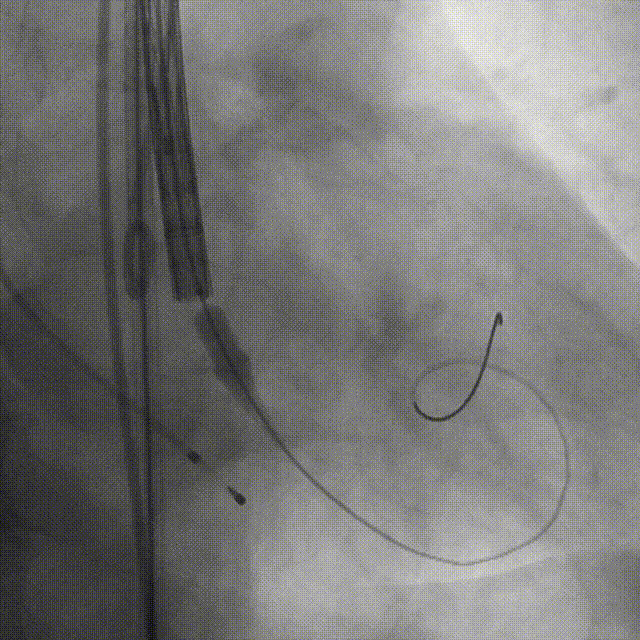

导丝跨瓣